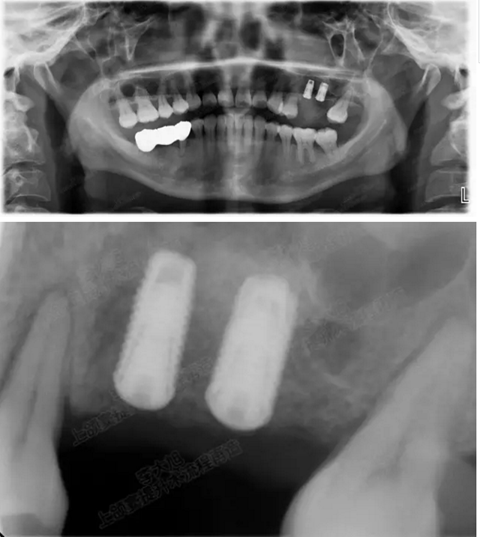

病例一

上頜竇多分隔3mm

05.png

提升8mm

06.png

07.png

修復(fù)時根尖片

08.png

09.png